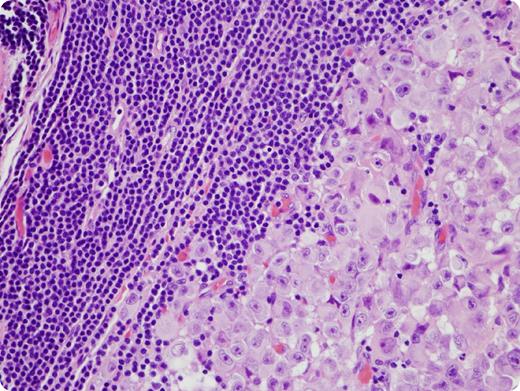

A 39-year-old man noted a pigmented lesion on his back that had been growing for ∼1 year. A punch biopsy demonstrated malignant melanoma, nodular type. He was also found to have a white blood cell count of 45.8 × 103/μL and palpable axillary, cervical, and inguinal lymph nodes. The blood was sent for flow cytometry and demonstrated a population of small CD19+ B cells that were λ light chain restricted, CD5+, CD10−, and CD23+ consistent with chronic lymphocytic leukemia/small lymphocytic lymphoma (CLL/SLL). Surgical pathology received bilateral axillary contents and a wide excision of the melanoma on the back. The lymph nodes grossly demonstrated areas that were pink-tan and fish-fleshy and other areas that were darkly pigmented. Of the 84 lymph nodes that were microscopically evaluated, 43 were involved by melanoma, and all were involved by CLL/SLL.

This case demonstrates an unusual circumstance of 2 primary malignancies present in the same specimen. Interestingly, BRAF mutations have been reported in both malignancies. Testing for BRAF mutations was performed on the punch biopsy and a bone marrow biopsy involved by CLL/SLL. The punch biopsy demonstrated a V600K BRAF mutation; however, a BRAF mutation was not detected in the bone marrow biopsy.